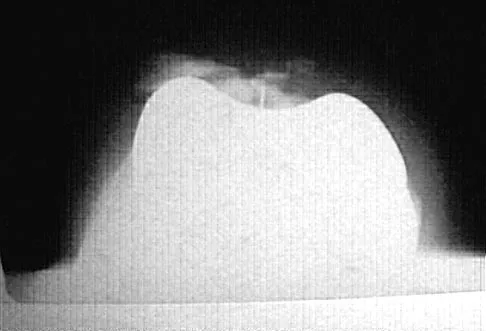

Consider the theoretic articulation shown in Figure 11 as femoral and tibial components of a total knee prosthesis in which the components fit like a "roller in trough." Which of the following best describes the articulation?

Explanation